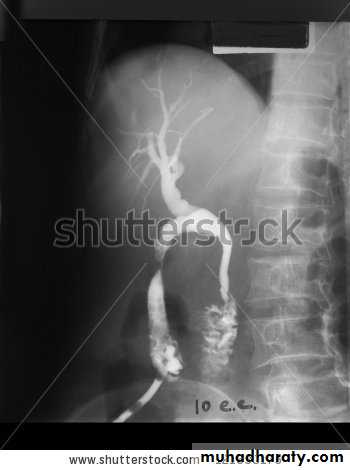

Percutaneous transhepatic cholangiography (PTC)

Under a local anaesthetic, a fine flexible needle is passed into the liver. Contrast is injected slowly until a biliary radicle is identified. Now this test rarly used due to high risks of bleeding, cholangitis and septicemia.Endoscopic retrograde cholangiopancreato-

graphy (ERCP)This technique is used to outline the biliary and pancreatic ducts. It involves the passage of an endoscope into the second part of the duodenum and cannulation of the ampulla. Contrast is injected into biliary systems and the patient is screened radio logically. diagnostic and therapeutic procedures can be carried out: like biliary stone removal , CBD stenting or biopsy taken.